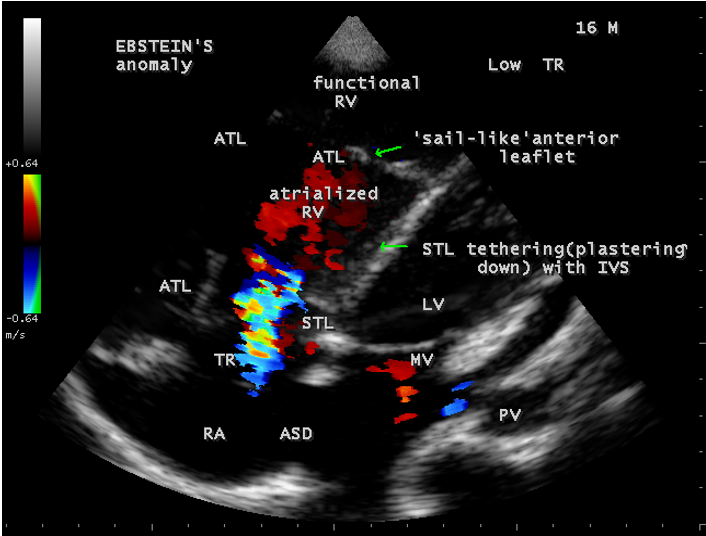

Case 1 (16-year-old cyanotic male with Ebstein’s anomaly) A 16-year-old male presented with cyanosis and he had features of an atrial septal defect such as wide, fixed splitting of second heart sound at left second intercostal space and a grade 2/6 systolic murmur at the lower left sternal border. 2D echocardiography revealed the features of Ebstein’s anomaly such as tethering of septal tricuspid leaflet (STL) to the ventricular wall associated with an ostium secundum type atrial septal defect (ASD) and low mild tricuspid regurgitation jet as shown in Figures 1 to 3

The anterior tricuspid leaflet is not involved in the process of downward displacement, it may be abnormally inserted occasionally and Shiina, et al documented the apical displacement of anterior tricuspid leaflet in 14% of cases echocardiographically [39]. The anterior leaflet forms a large, sail-like intracavitary curtain as in Figures 14, 25 and contains muscular strands instead of consisting entirely of a fibrous membrane as in the normal tricuspid valve [40]. It is potentially mobile with a brisk sail-like movement as shown in Figure 21 to 24 [41], free bloating with a ‘whipping motion’ across the right ventricular outflow tract (RVOT) as shown in Figure 26 and in some cases, the movement is restricted due to its adherence to the ventricular wall as in Figure 1 and 2, 4 and 9. It is often fenestrated, may in part be musculaized , inserting into the trabeculations of the right ventricle (RV) as in Figure 28 and rarely, the anterior leaflet forms an ‘atretic’ membrane that spans the midportion of the right ventricular cavity as in Figure 16.

The tricuspid orifice is typically incompetent as in Figures 3, 5 and 10, occasionally stenotic, and rarely imperforate as in Figure 16 [44],[45]. The true anatomic tricuspid annulus occupies its normal position at the right atrioventricular junction and it is less well defined than in a normal heart. The annulus tends to be appreciably dilated and contribute to the development of valvular incompetence. In extreme downward displacement of posterior and septal leaflets, the closure of the tricuspid annulus depends on the size and potential excursion of anterior leaflet. When the chordal attachments are short and the leaflets contain multiple or large fenestrations, adequate valve closure is impossible to achieve and varying degrees of regurgitation results. Color flow imaging and Doppler interrogation can establish the relatively low velocity regurgitant flow as in Figure 6, which begins at the level of the displaced septal and posterior leaflets as in Figures 5 and 10 and courses through the atrialized right ventricle into the right atrium proper as shown in Figure 5. Tricuspid regurgitation increases by annular dilatation [46]. During contraction of the atrium, the atrialized portion of the right ventricle balloons out and acts as a passive reservoir. Functional improvement of right ventricle depends on the severity of tricuspid regurgitation and on the ratio of the combined areas of right atrium and atrialized right ventricle relative to the areas of functional right ventricle and left ventricle [47]. Celermajer, et al described an echocardiographic grading score for neonates with Ebstein’s anomaly as shown in the Table 5 [48].